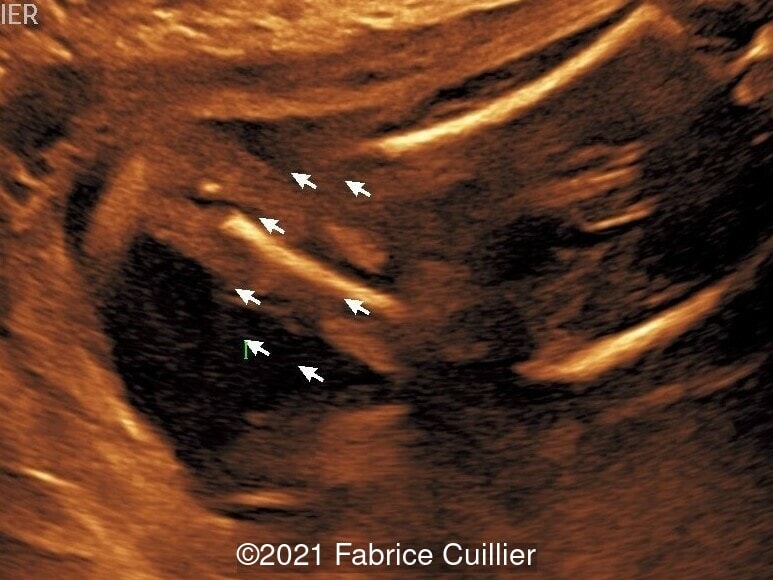

• Images 2-4: Ultrasound at 22 weeks gestation showing left foot edema with narrowing and stricture of the soft tissue due to an amniotic band (marked as ? on image 2).

• Images 5-7, video 1: Ultrasound at 23 weeks gestation showing similar finding to images 2-4.